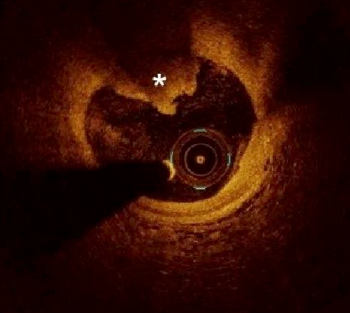

光学相干断层成像OCT)是一种高分辨率的冠脉血管腔内成像技术,利用近红外光照射血管壁,通过测量反射光的时间延迟和强度,生成高分辨率的横断面图像。OCT的分辨率可达10-20微米,比传统的血管内超声(IVUS)高10倍,能够清晰显示血管壁的微观结构。

冠脉造影显示狭窄病变             血管腔内影像显示极易破裂的斑块

血管腔内影像显示斑块侵蚀            血管腔内影像显示钙化结节